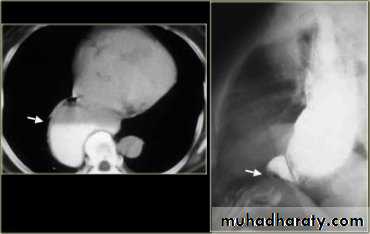

Sliding herniaOn the left initially, GE junction is below the esophageal hiatus. Later, stomach protrudes through hiatus

Para esophageal hernia

On the far left gas filled gastric funds (asterisk) protrudes through hiatus but GE junction (arrow) is below diaphragm